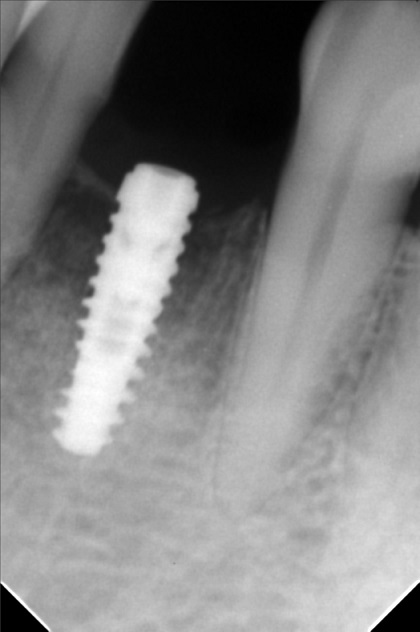

- Procedure

- george_escala_01.jpg

- george_escala_02.jpg